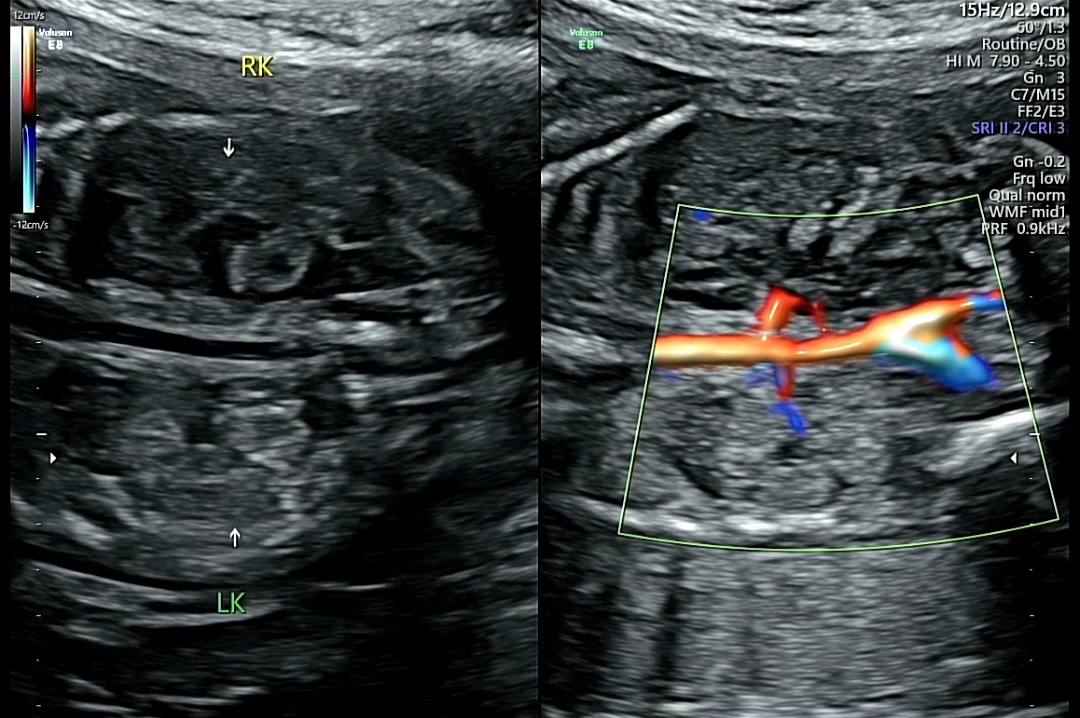

3. 신장 발달 및 혈류 확인

1) RK(Right Kidney, 오른쪽 신장) : 정상 발달 확인

2) LK(Leftt Kidney, 왼쪽 신장) : 정상 발달 확인

3) 컬러 도플러 영상 : 빨강, 파란색은 혈류의 흐름을 나타냄. 양쪽 신장으로 혈액이 잘 공급되는지 확인